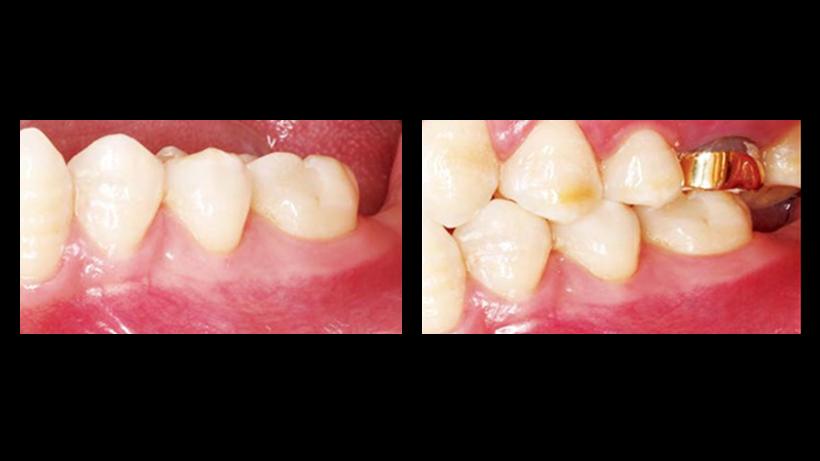

Clinical case: Single molar implant with bone augmentation

- Courtesy of Dr. Jung Sam Lee, Korea -

Keywords

AnyOne, bone augmentation, osteotomy socket, peri-implant tissue, autogenous bone, GBR, single replacement, Auto-Max, Dr. Jung Sam Lee

Products:

AnyOne implant system, Auto-Max